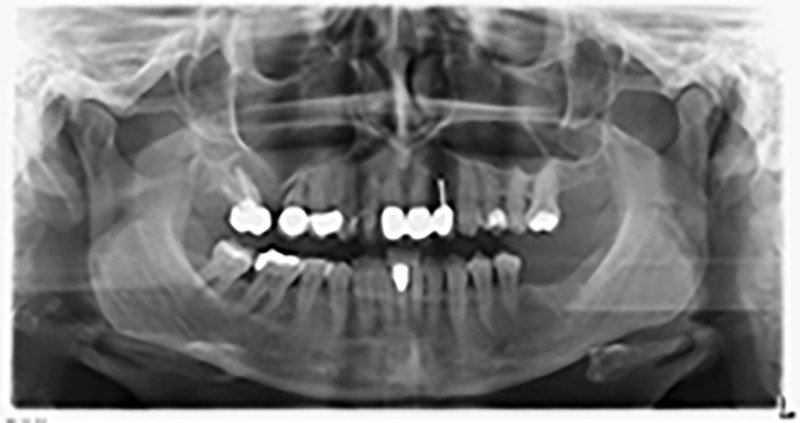

The 59-year-old patient presented with an advanced case of periodontitis, describing an unpleasant feeling and poor taste from the first quadrant in a distal direction. The clinical examination revealed generally enlarged periodontal pockets and very advanced bone atrophy in regions 16 and 14. The radiology confirmed the findings (Fig. 1). Teeth 16 and 14 could not be retained.

About six months after teeth 16 and 14 were extracted, a digital volume tomography (DVT, Planmeca) examination was performed for planning and risk minimization purposes. It clearly showed that the bone had not regenerated to the desired volume (Fig. 2 to 7).